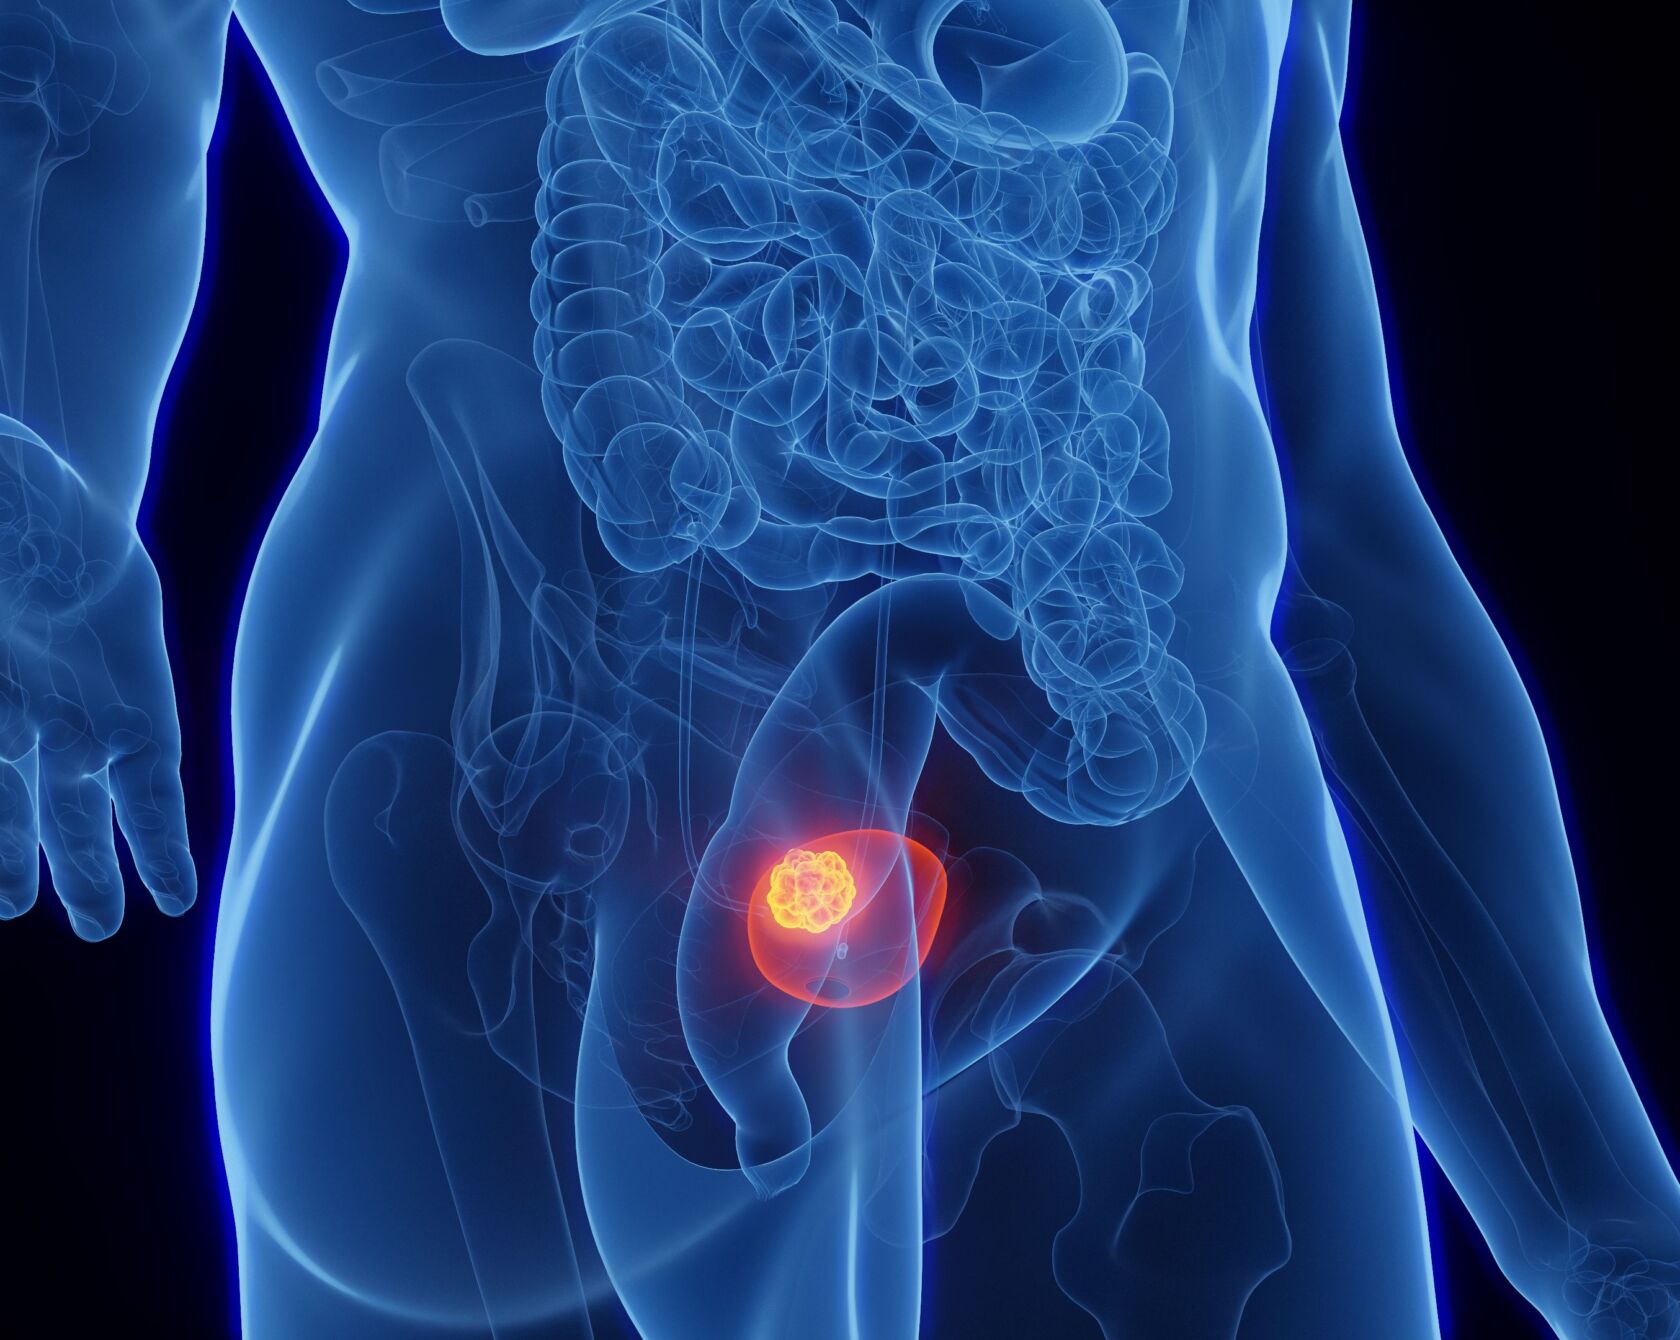

Die adjuvante Instillationstherapie hat sich bei Patienten mit nicht-muskelinvasivem Blasenkrebs (NMIBC) bewährt. Bei BCG-Versagen bietet die neue Kombinationstherapie mit Gemcitabin und Docetaxel eine vielversprechende Alternative, die auch eine Blasenerhaltung ermöglichen kann.

Die adjuvante intravesikulare Instillationstherapie ist eine wirksame Behandlungsoption für viele Patienten und Patientinnen mit nicht-muskelinvasivem Blasenkrebs (NMIBC). Bei der Instillationstherapie werden Immun- oder Chemotherapeutika in flüssiger Form direkt über einen weichen Katheter in die Blase eingebracht, statt oral oder intravenös verabreicht zu werden. Diese Methode maximiert die Wirksamkeit der Behandlung, während potenzielle Nebenwirkungen minimiert werden, da die Medikamente nicht durch andere Körperregionen gelangen müssen, um die Blase zu erreichen.

Bei der Instillationstherapie mit Bacillus Calmette-Guérin (BCG) wird die Blase mit Bakterien gespült, die das Immunsystem anregen und so als Immunmodulatoren fungieren. Sie ist die bisher wirksamste Instillationstherapie. Dennoch kann es zu Therapieversagen kommen und es können Rezidive in der Blase auftreten. Bei BCG-Versagen wird als nächste Therapiestufe normalerweise eine radikale Zystektomie empfohlen. Für Patienten und Patientinnen, die eine Blasenerhaltung bevorzugen oder nicht für eine Operation geeignet sind, steht jetzt eine neue alternative Salvage-Instillationstherapie zur Verfügung.